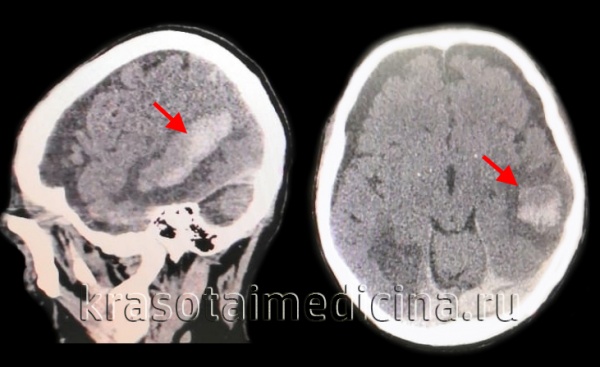

КТ головного мозга позволяет выявить объем и локализацию интрапаренхиматозной гематомы, степень смещения мозга и наличие отека, а также область кровоизлияния. Рекомендуется проводить повторные КТ-исследования для отслеживания изменений гематомы и состояния мозговой ткани.

Золотым стандартом для диагностики является компьютерная томография (КТ). В первые 1-3 дня после приступа этот метод нейровизуализации более информативен, чем МРТ. Свежий геморрагический материал, содержащий 98% гемоглобина, на КТ выглядит как высокоплотное, четко очерченное, ярко-светлое включение на фоне более темной мозговой ткани. На основе компьютерной томограммы определяются зона эпицентра, объем и форма образования, уровень поражения внутренней капсулы, степень смещения мозговых структур и состояние ликворной системы.